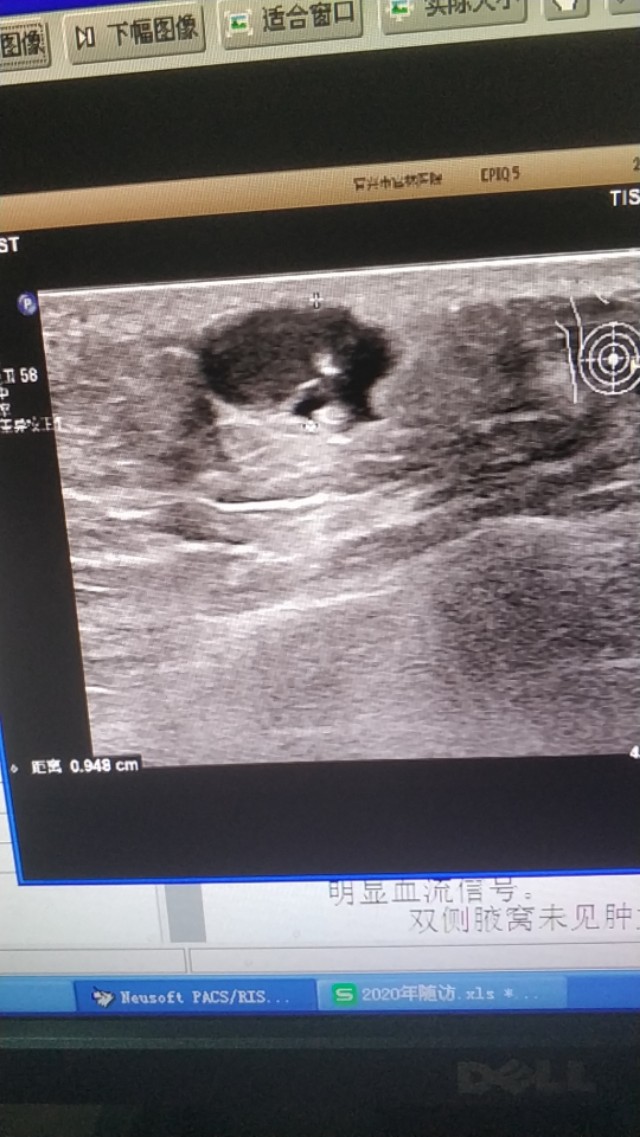

上面是一张胸壁的表皮囊肿,边缘不光滑,下方有液性暗区,这是一个表皮囊肿破裂的病例的。

(这两个病例是上个月随访的)